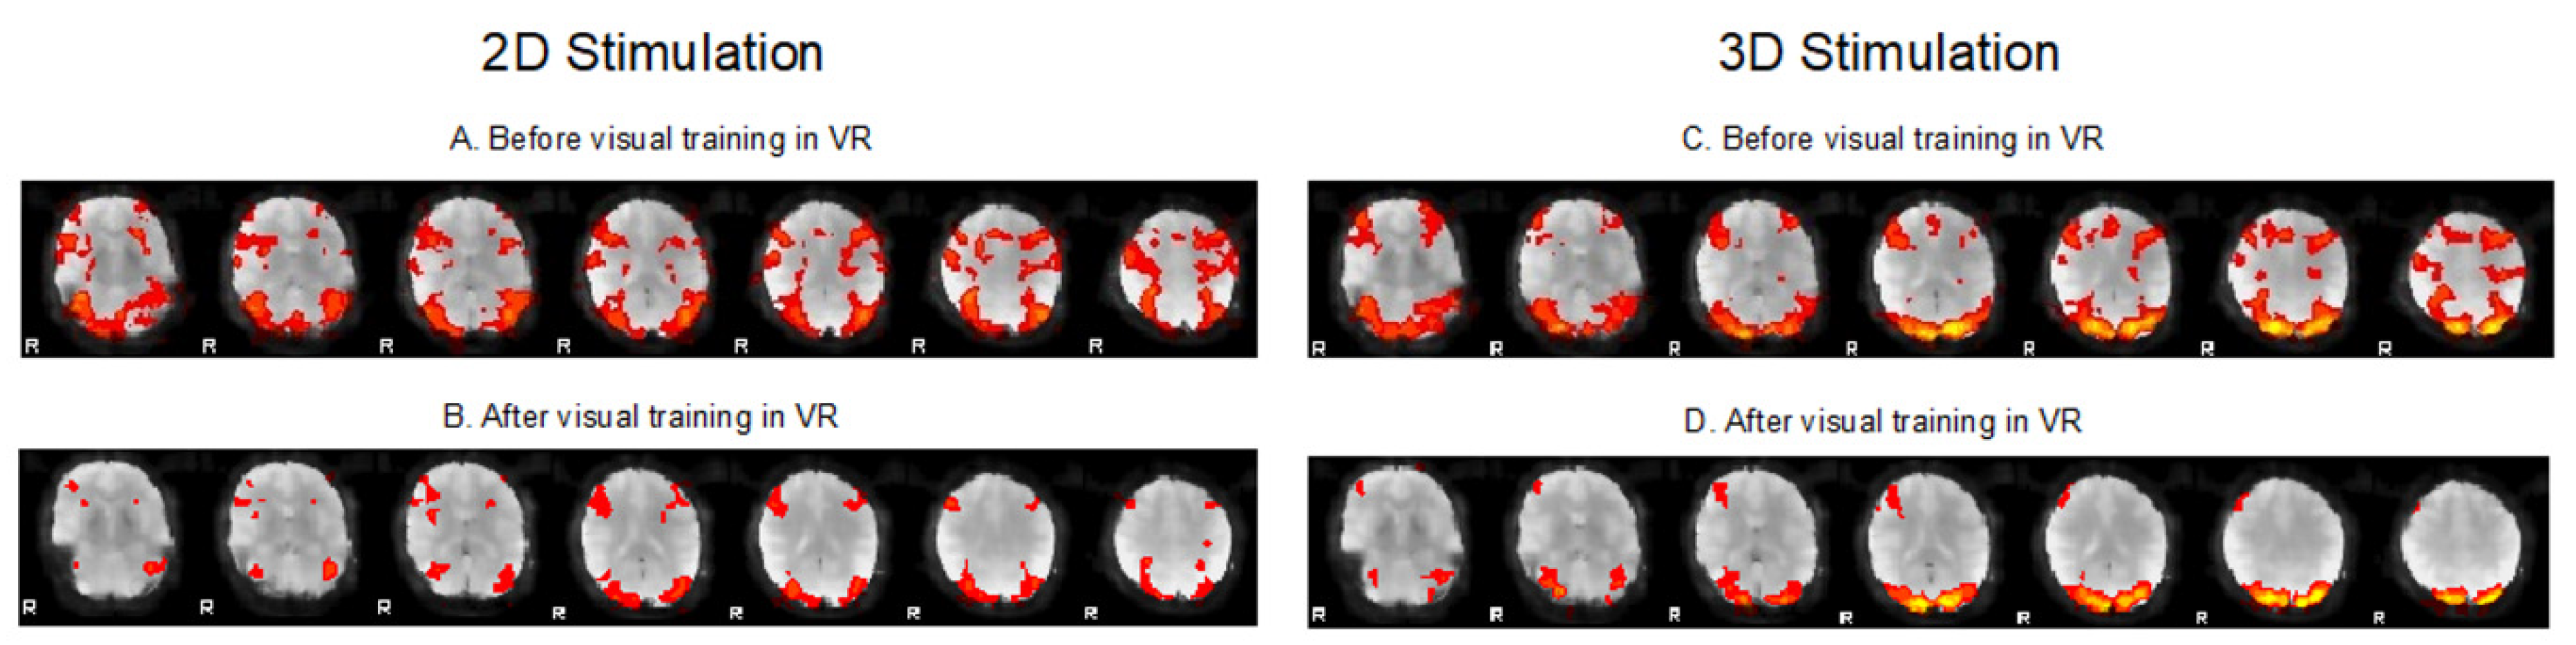

1. Introduction

2. Case Report

2.3. fMRI Testing

3. Discussion